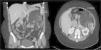

Clinical ObservationA 33-year-old woman was referred to us as a candidate for LTx due to persistent right pneumothorax in spite of endothoracic drainage. The patient was an ex-smoker whose accumulated consumption was not very significant. She had had right pneumothorax during the year prior to the consultation and early relapse after the endothoracic drain had been withdrawn. Initially, she did not present respiratory failure and spirometry detected a severe obstruction with air trapping and hyperinflation. Radiological studies demonstrated bilateral interstitial pattern with presence of multiple small-sized, thin-walled cysts that affected the entire pulmonary parenchyma, with a preserved architecture. With the clinical suspicion for LAM, the patient presented left pneumothorax and collapsed lung. Mechanical pleurodesis was carried out and open lung biopsy confirmed the diagnosis. Given the deterioration of the lung function and the presence of a new right pneumothorax with persistent loss, the patient was referred to our Lung Transplantation Unit. During the evaluation, an abdominal CT detected a mass with heterogeneous density in the left kidney compatible with a renal angiomyolipoma (Fig. 1) and cystic lesions in the liver. She was included on the preferential national waiting list for LTx and, days later, underwent right single-lung transplantation with no immediate complications.